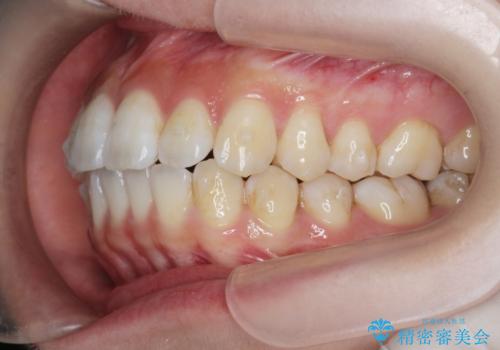

- 前歯の噛み合わせの開きの改善を求めて来院されました。

奥歯はほとんど動かさず(奥歯の噛み合わせはほとんど変えず)前歯のIPR矯正でガタつき前突感(出っ歯感)の改善を計画します。

ほとんど前歯のみの矯正治療であることからトータル14枚のマウスピースで並べるインビザラインライトによる治療を行います。

インビザラインライトは全14枚のマウスピースで行う軽度なガタつきなどの改善を目的とする矯正治療です。(約3.5ヶ月)

今回の治療では追加でマウスピース治療を行なったため、半年弱の治療期間となりました。